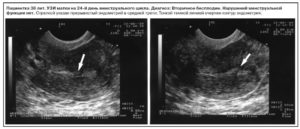

Фемостон тонкий эндометрий при гистероскопии

Малоинвазивная методика осмотра внутренних поверхностей матки, с общей оценкой ее состояния, проводится перед началом приема специализированных препаратов для увеличения толщины эндометрия. Фемостон является гормональным средством, которое предназначено для решения указанной проблемы.

Диагностирование патологии

При обращении за профессиональной помощью пациентка отправляется на консультацию к гинекологу. Врач проводит сбор основных данных, внося их в историю болезни. После выставления предварительного диагноза больная направляется на ультразвуковое обследование матки, сдает анализы на показатели гормонального фона, клиническое исследование мочи и крови.

Наиболее эффективными диагностическими мерами при данной патологии считаются:

- Ультразвуковая сонография – при нормальной ситуации обнаруживается трехслойная клеточная структура, которая позволяет забеременеть (хотя вероятность не превышает 25%), даже если слизистая оболочка истощена (меньше 5 мм) и понизить вероятность выкидыша. Когда эхопризнаков трехслойной формации нет, беременность не наступает.

- Гистероскопия – дает возможность исследовать полость матки и получить образец биопсийного материала с целью морфологического исследования, чтобы изучить структурные преобразования.